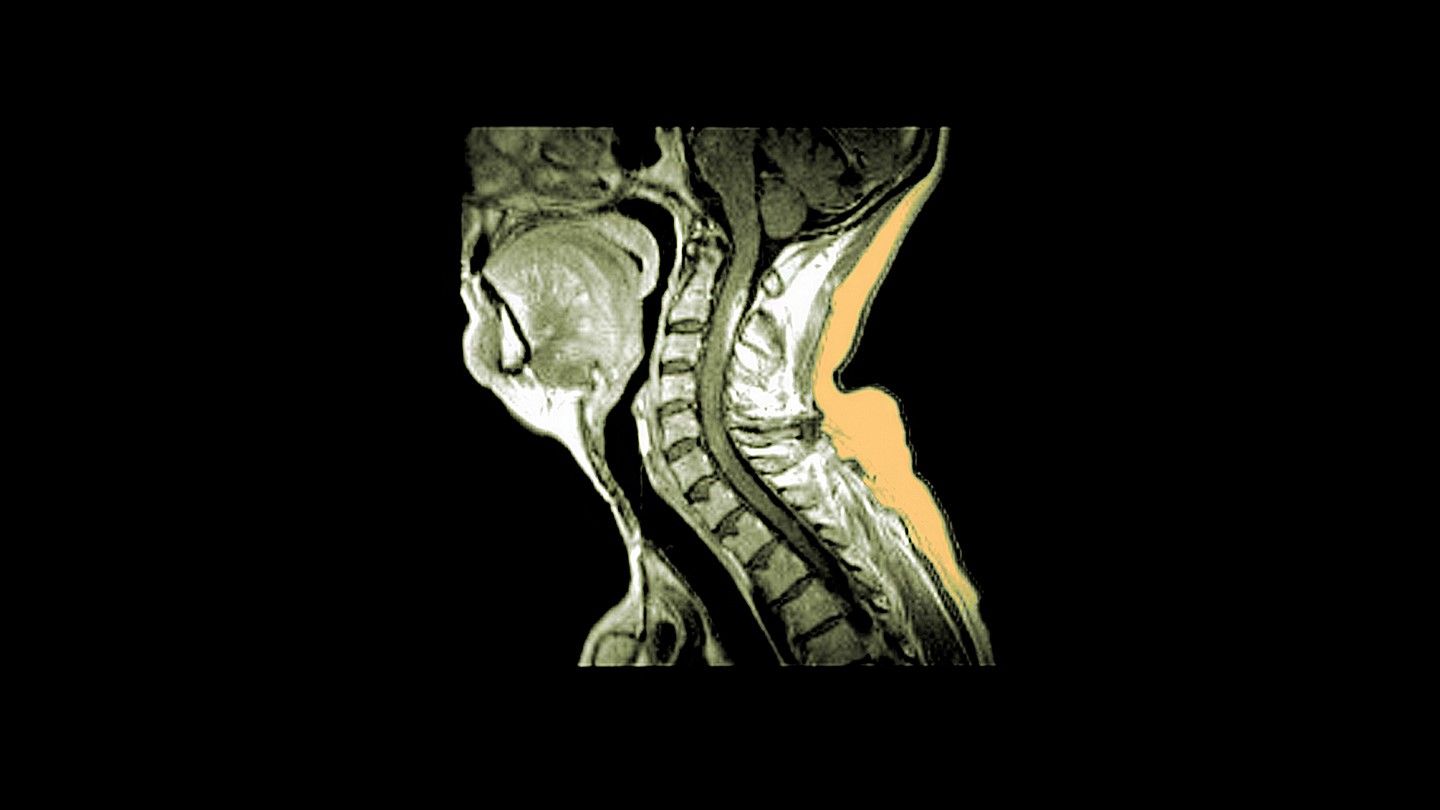

The spinal cord has less reserve than the brain because it has a much smaller cross-sectional area which reduces its ability to rewire, though lesions can repair themselves, so spinal lesions can be more problematic than brain lesions. Some spinal lesions do not produce any symptoms though. However, it really depends on how active the MS is in the spinal cord. The more lesions that develop will increase the risk of disability. Treatment that reduces inflammation and slows down MS is something that should be seriously considered.

I have no expert knowledge, but my understanding is that there is room in the brain for a lesion to cause no trouble if you are very lucky. There’s less room in the tightly-packed spinal cord for a that kind of luck to happen.